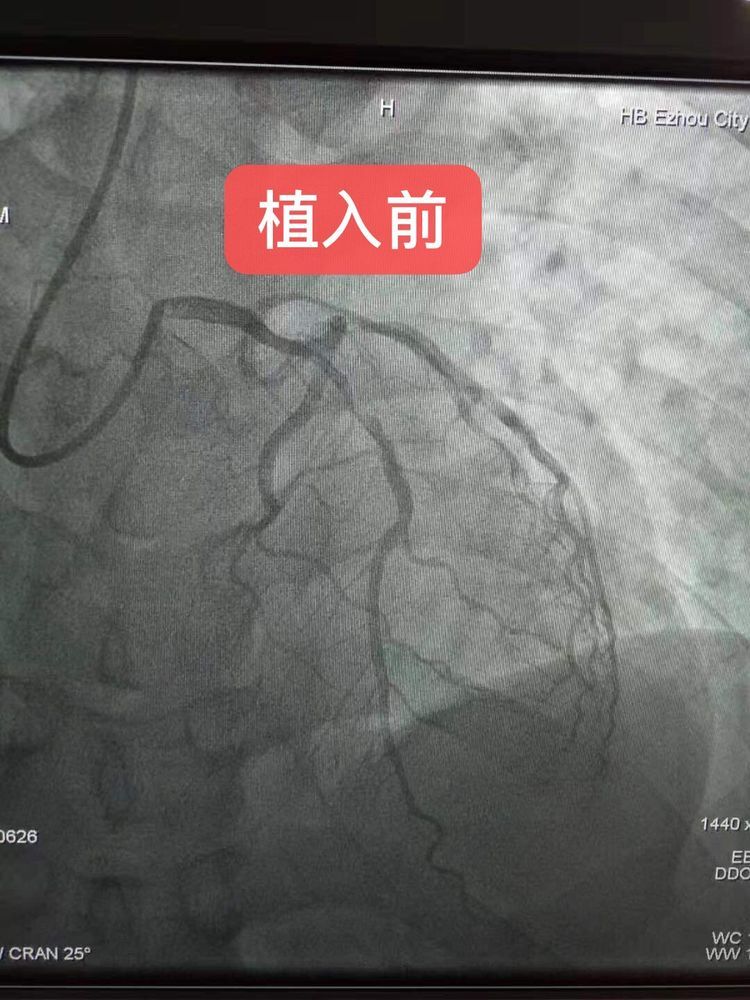

2019年9月19日,年仅36岁患者,因急性心肌梗死收治我院心内科。造影显示患者左冠前降支堵塞80%左右,鄂州中医医院洪苍浩主任,在武汉大学中南医院胡笑容教授的指导下,为这名年轻患者植入两枚生物可吸收支架(支架串联),手术非常成功!这是鄂东南地区首例,也是湖北省中医系统医院首例。(患者术后与两位术者合影,表示感谢)